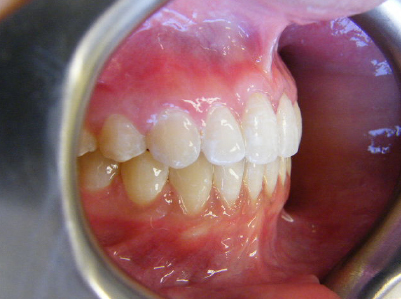

Patient 2: Significant increased overjet and upper and lower crowding.